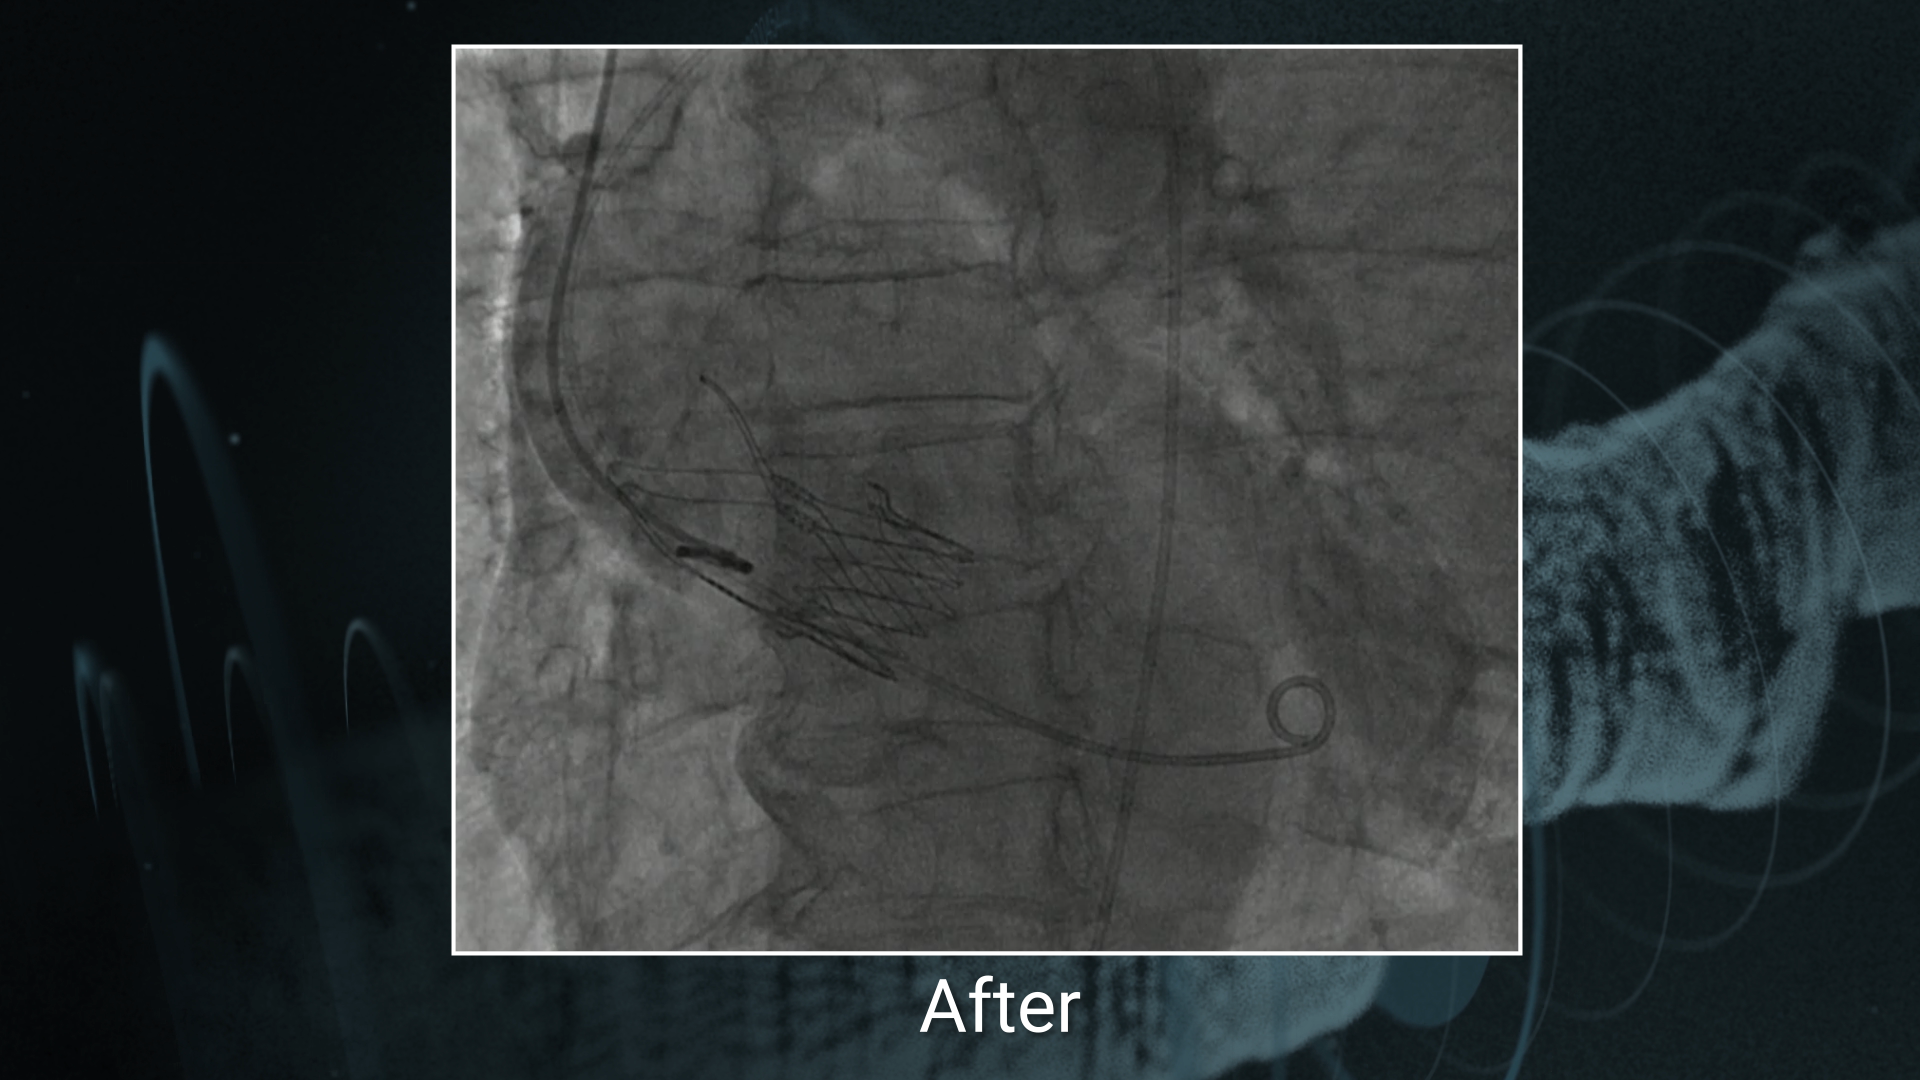

• venkatesa reddy D. very well demonstrated how to treat double bifurcation in simple method

MEGATRON in Ostial & LM lesions / ACURATE neo in TAVI